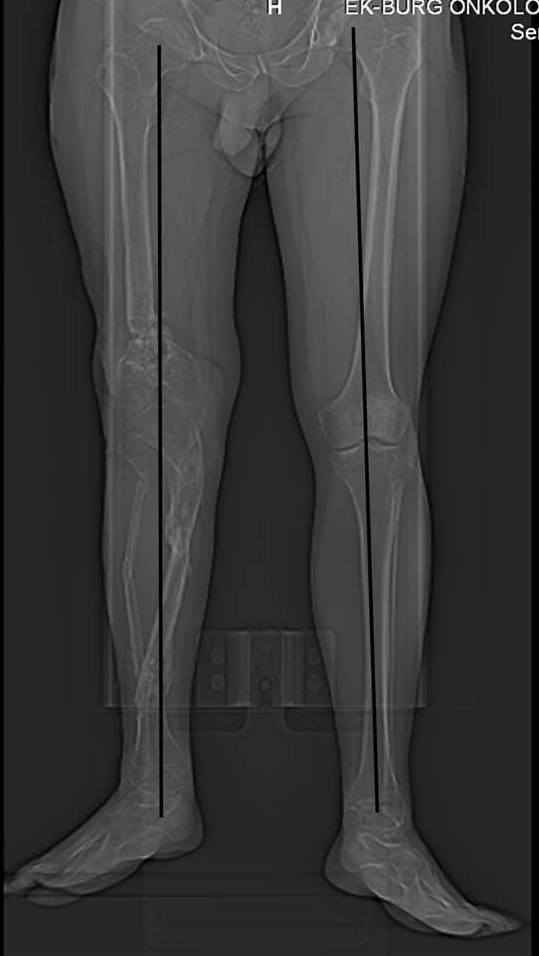

Псевдоартроз дистального отдела бедра. Distal femur nonunion (продолжение http://weborto.net/forum/1293474476/index_html) Относительное укорочение - 6,1 см по КТ, осевую реконструкцию прилагаю (возможно не совсем корректная, но общее представление составить можно). P.S. Прошу прощения. за возобновление темы, появились новые данные, а интерес угас, но, как кажется, проблема интересная